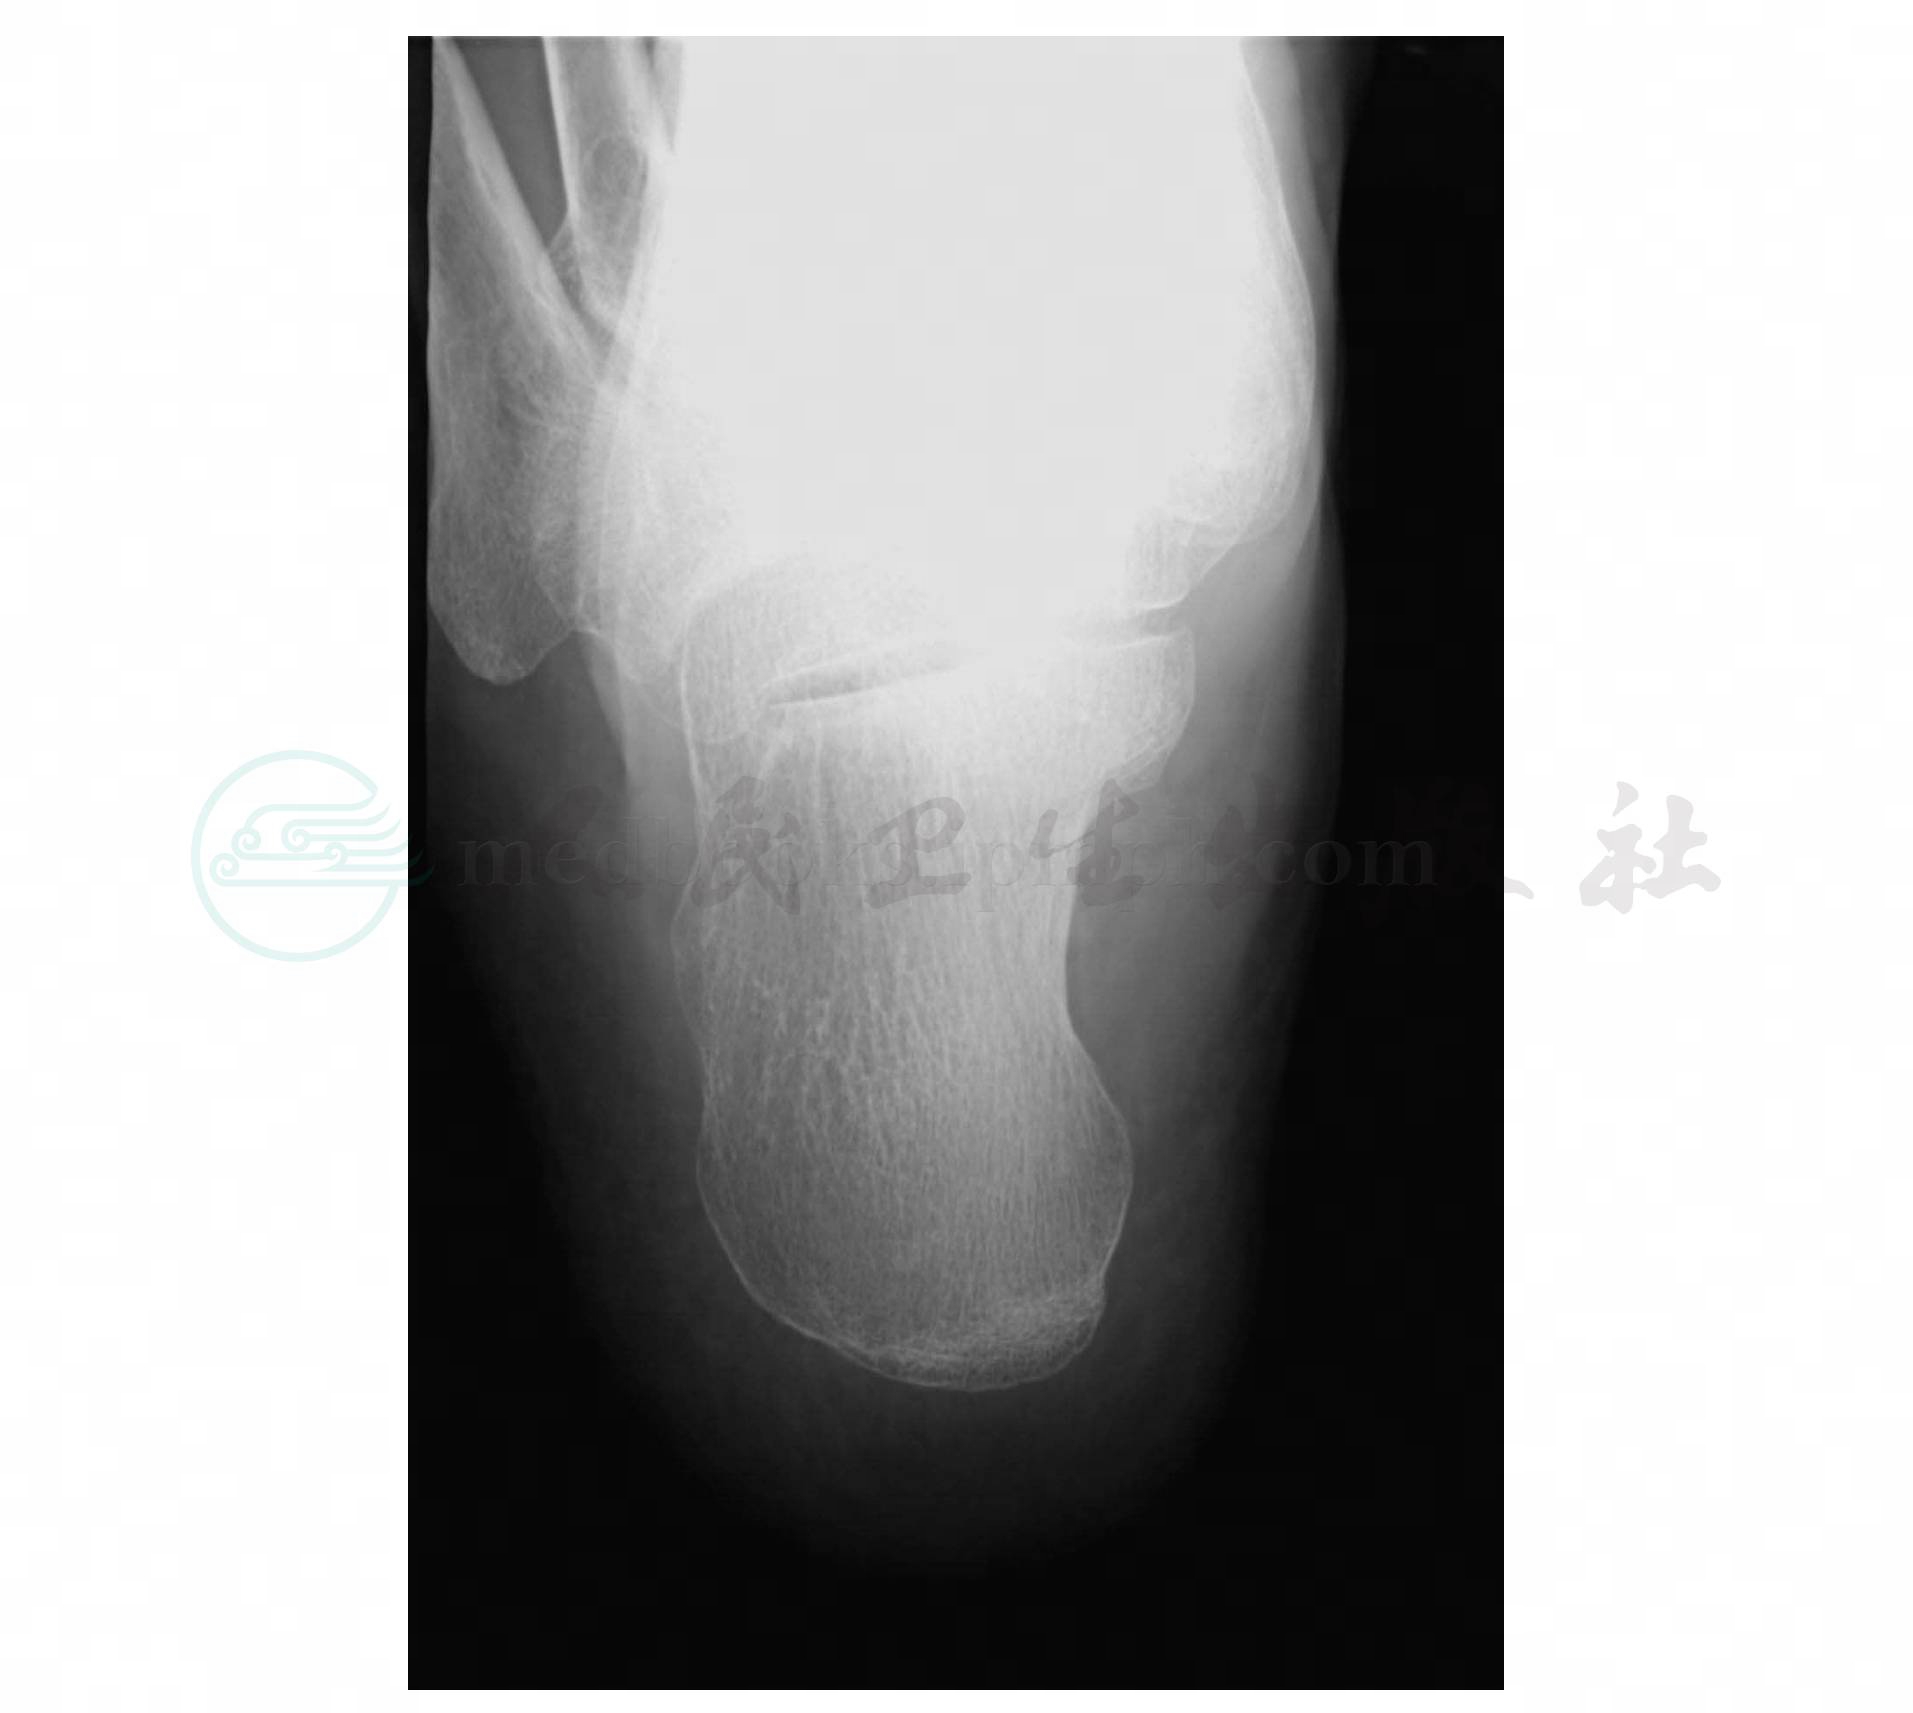

显示跟骨轴位像,跟距关节显示清晰(图1、图2)。

图1 跟骨底跟轴位显示图

图2 跟骨底跟轴位照片图